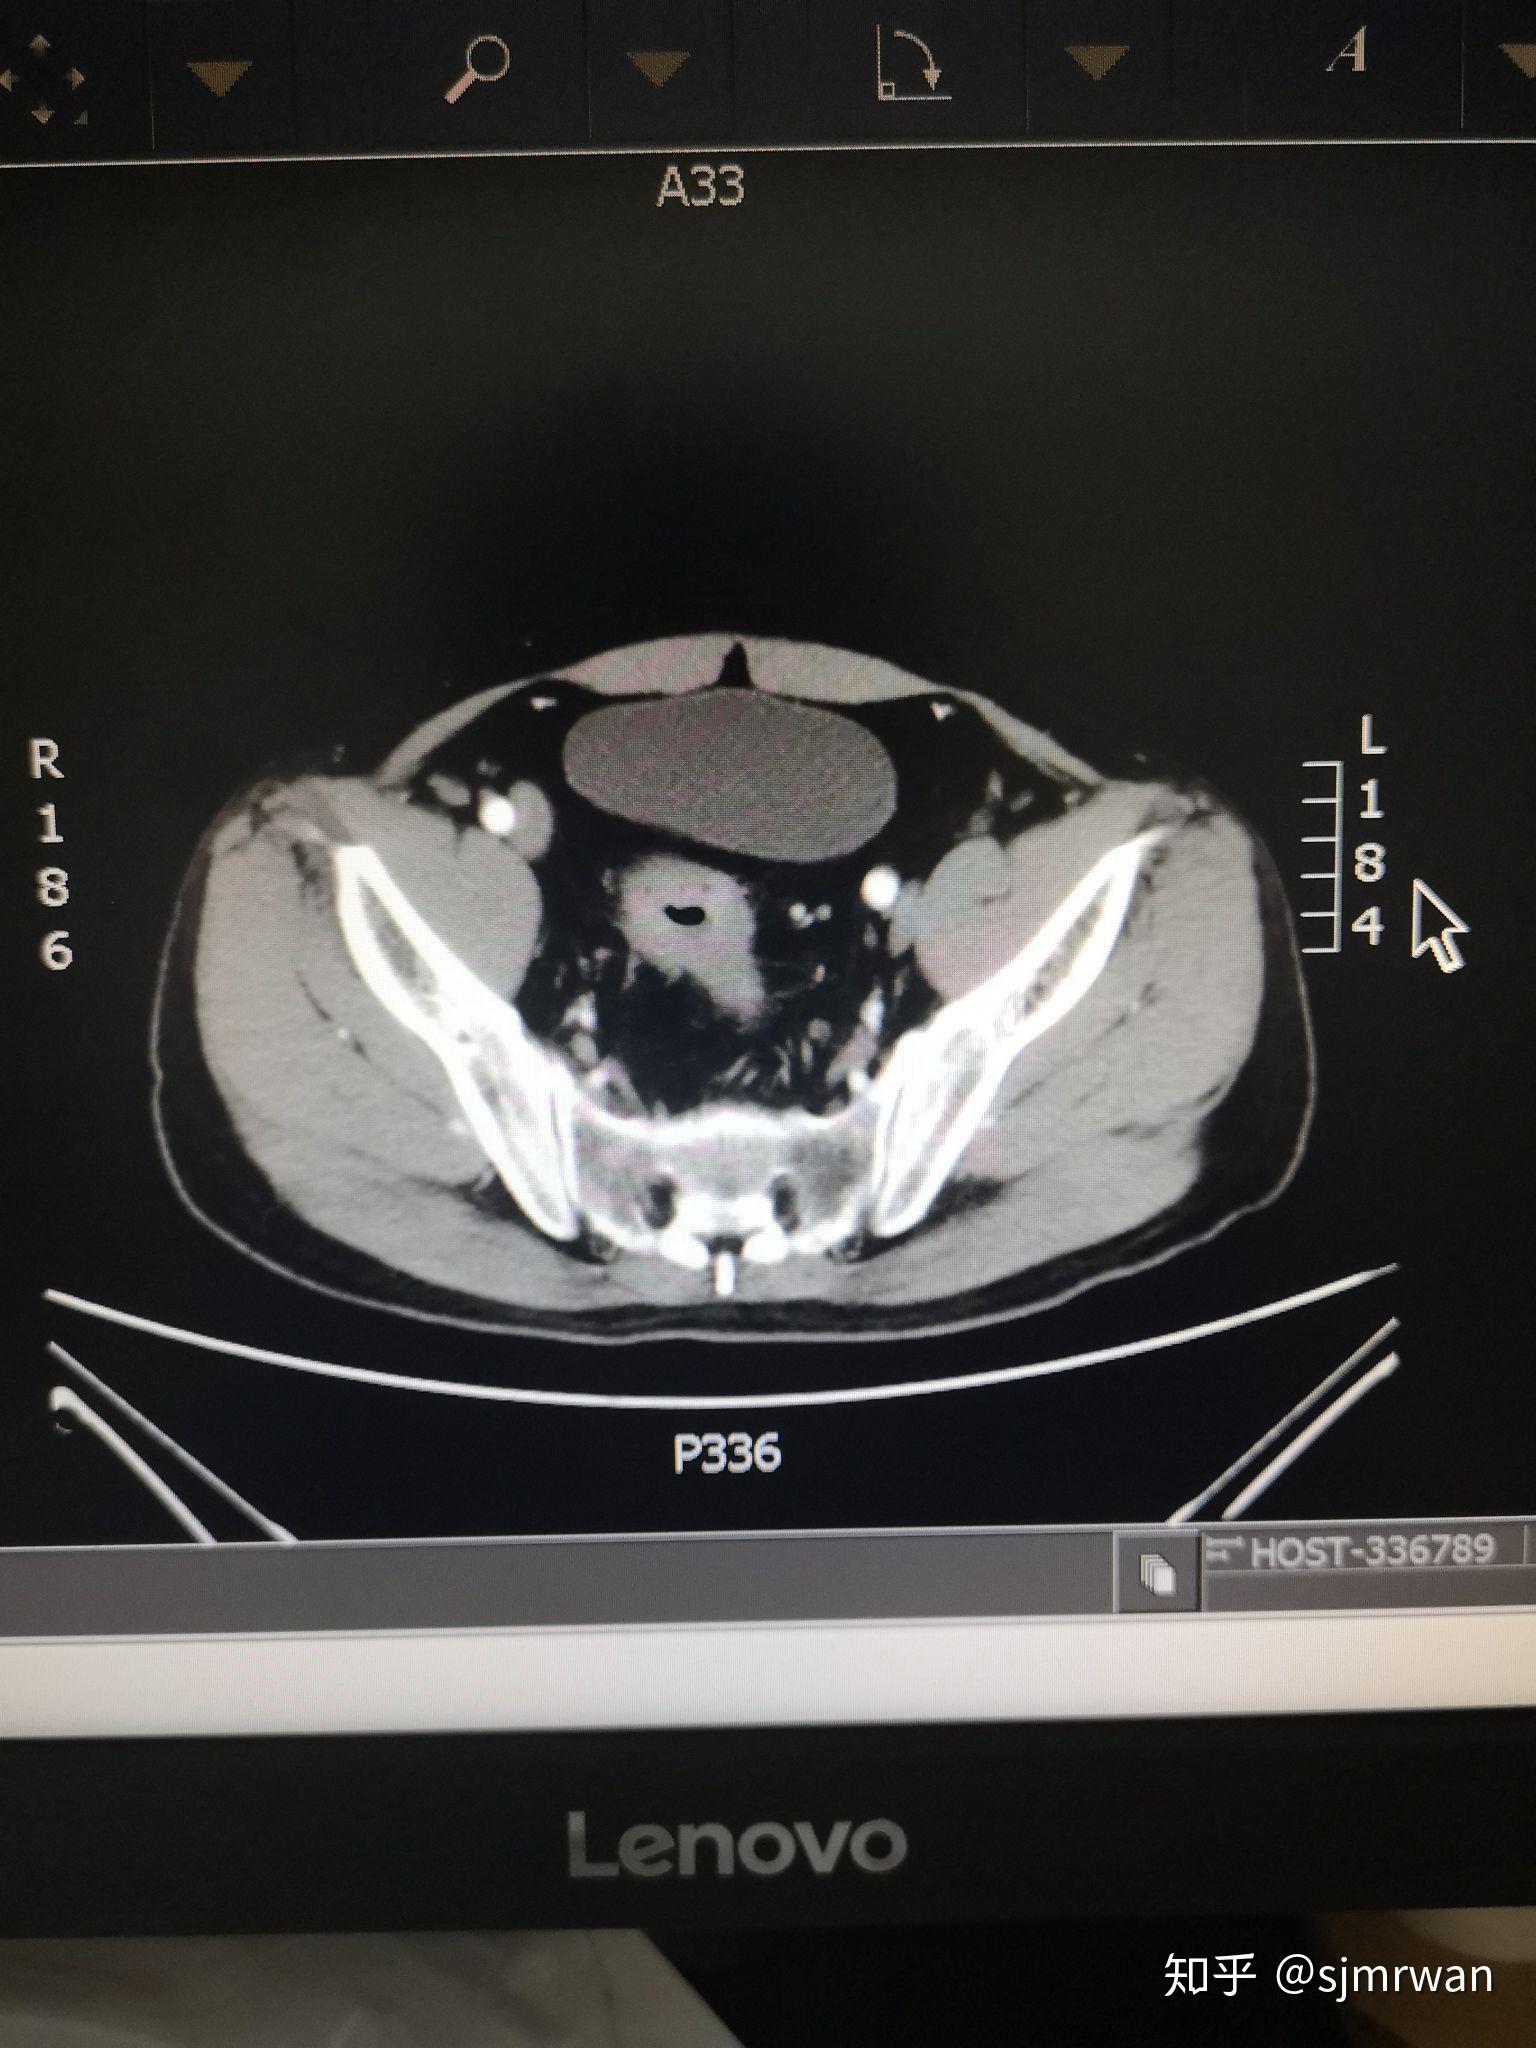

直肠癌一例 - 知乎

图片尺寸1536x2048